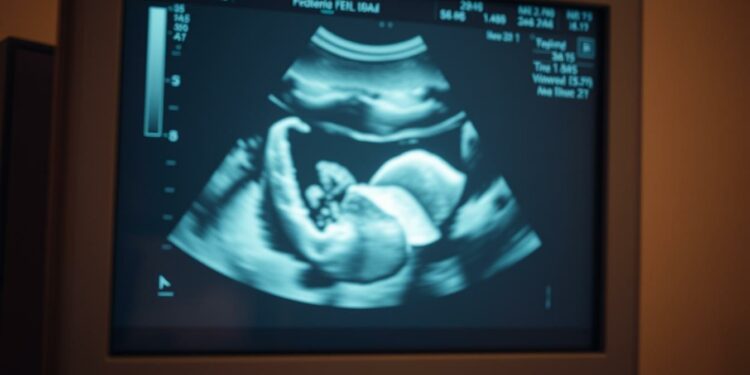

In der 5. Schwangerschaftswoche kann der Ultraschall lediglich eine verdickte Gebärmutterschleimhaut und die Fruchthöhle als dunklen Fleck zeigen. Manche Embryonen sind möglicherweise so positioniert, dass sie schwerer zu erkennen sind. Deshalb kann es vorkommen, dass beim ersten Ultraschall kein Embryo bei 5. Schwangerschaftswoche Ultraschall sichtbar ist. Ein Folgetermin hilft dabei, die Entwicklung der Schwangerschaft weiter zu verfolgen.

Während des frühesten 5. Schwangerschaftswoche Ultraschall unauffällig kann man meist nur die Fruchthöhle und den Dottersack erkennen. Diese kleine schwarze Fruchthöhle ist in der Regel etwa 1 cm groß, und der Embryo, der bis zu 2-4 mm groß ist, ist möglicherweise noch nicht sichtbar. Dies sollte jedoch weder Ärzte noch werdende Mütter beunruhigen.

Ultraschallgeräte nutzen hochfrequente Schallwellen, um ein Bild des inneren Körpers zu erzeugen. Diese Schallwellen werden von einem Transducer ausgesendet, durch den Körper geleitet und von den inneren Strukturen zurückgeworfen. Der Transducer empfängt die reflektierten Schallwellen und wandelt sie in elektrische Signale um, die dann ein Bild auf einem Monitor erzeugen. Diese Technologie erlaubt detaillierte Einblicke, besonders in der Frühschwangerschaft. Ein frühes Ultraschallbild Schwangerschaft kann wichtige Informationen über die Embryonalentwicklung bieten.

Der Einsatz von Ultraschall in der 5. Schwangerschaftswoche ist von entscheidender Bedeutung. In dieser Phase kann der Ultraschall genutzt werden, um die Position der Schwangerschaft zu bestätigen, die Größe der Fruchthöhle zu messen und erste Hinweise auf eine Herzaktivität zu identifizieren. Experte bemerkt, dass ein Ultraschall in der 5. Schwangerschaftswoche oft beruhigende Gewissheit für werdende Eltern bieten kann. Das frühe Erkennen von Anomalien oder Komplikationen ermöglicht zudem eine frühzeitige interventionelle Versorgung.

Ein fehlender Embryo bei 5 Wochen Ultraschall ist nicht unbedingt ein Grund zur Sorge. In der 5. SSW ist der Embryo sehr klein, etwa 1 Millimeter groß, ähnlich einem Pfefferkorn. Es ist möglich, dass im Ultraschall nur eine verdickte Gebärmutterschleimhaut, die Fruchthöhle und eventuell ein kleiner Punkt zu sehen sind, der den Embryo darstellt.